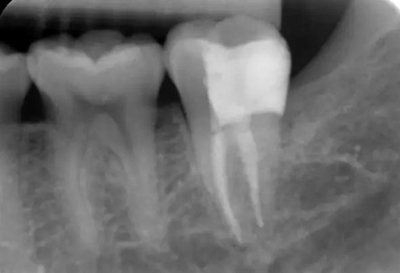

圖2 術(shù)前X片示遠(yuǎn)中鄰面牙體低密度影累及髓角

圖7 試主尖X線片

圖11 術(shù)后X線片:37恰填,遠(yuǎn)中鄰面樹脂充填物密合,無懸突。